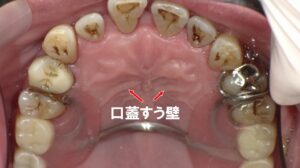

この写真は、上顎の口蓋(上あごの天井部分)を写したもので、赤い矢印が示しているのは 「口蓋皺壁(こうがいすうへき)」 と呼ばれるヒダ状の構造です。

口蓋皺壁は前歯のすぐ後ろに左右対称に並んでいる隆線で、個人差が大きいものの誰にでも存在する生理的な構造です。